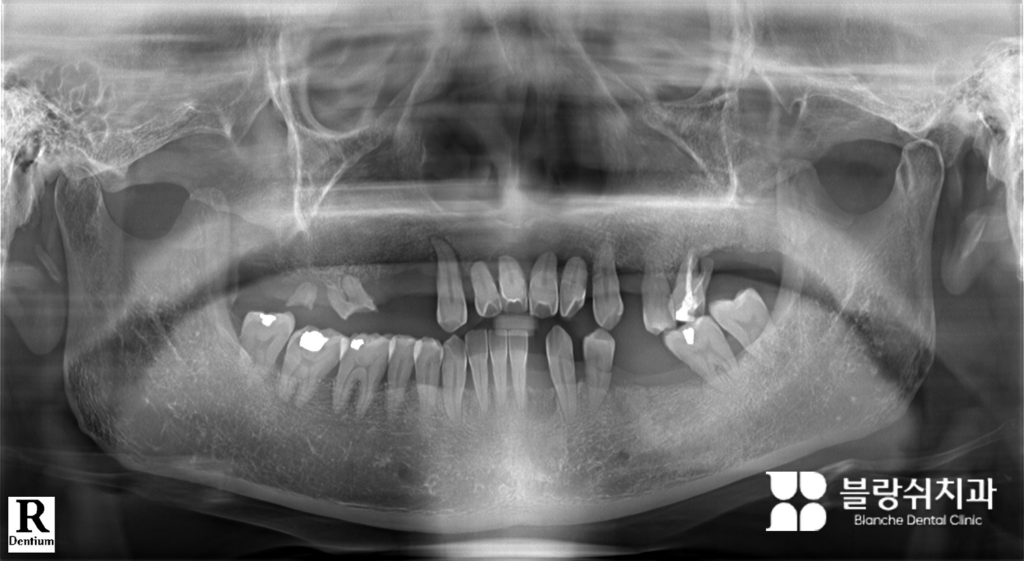

(1) 초기 진단 및 발치 결정

처음 내원 시 윗니 대부분이 흔들리거나 뿌리만 남은 상태였습니다. 오래 못 갈 치아가 많아 윗니 전체를 빼고 다시 만드는 게 불가피하다고 판단했습니다. “남은 치아를 꼭 빼야 하나요?”라는 질문을 많이 받습니다. 치아를 살리는 게 항상 좋은 선택은 아닙니다. 오래 못 갈 치아를 억지로 남기면 오히려 전체 씹는 균형이 무너지고, 나중에 더 큰 문제를 만들 수 있습니다.